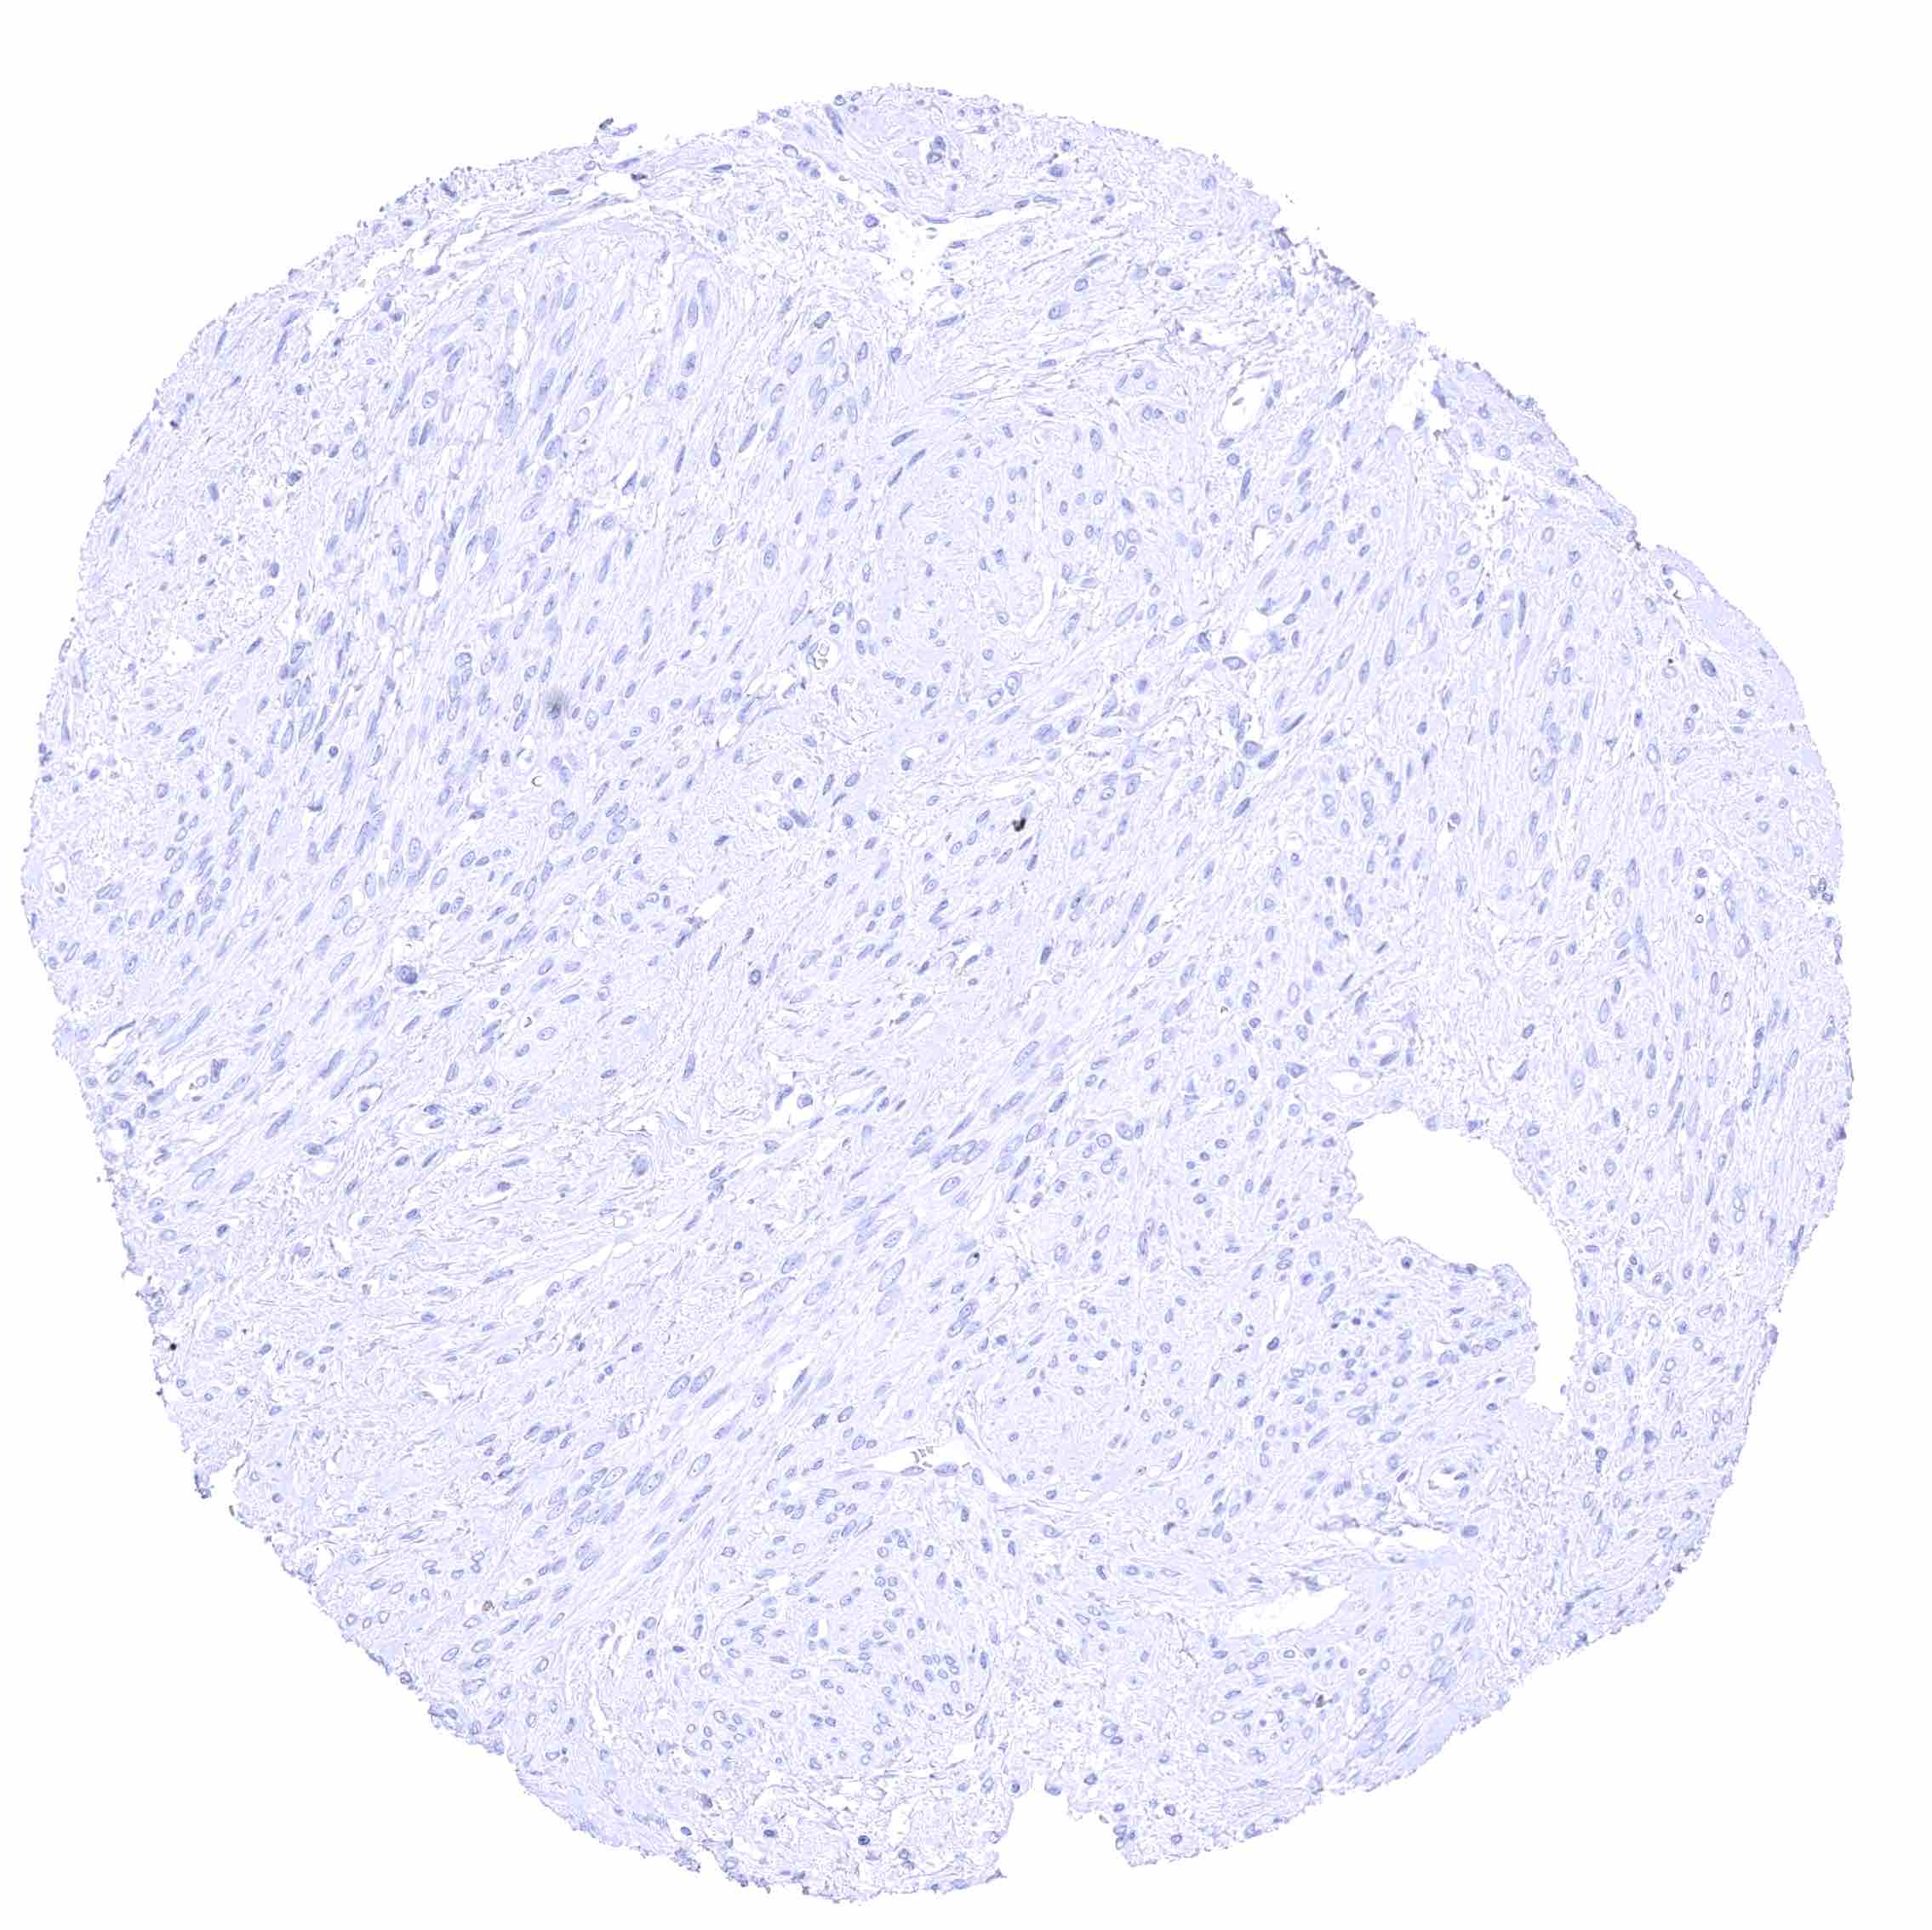

Uterus, myometrium